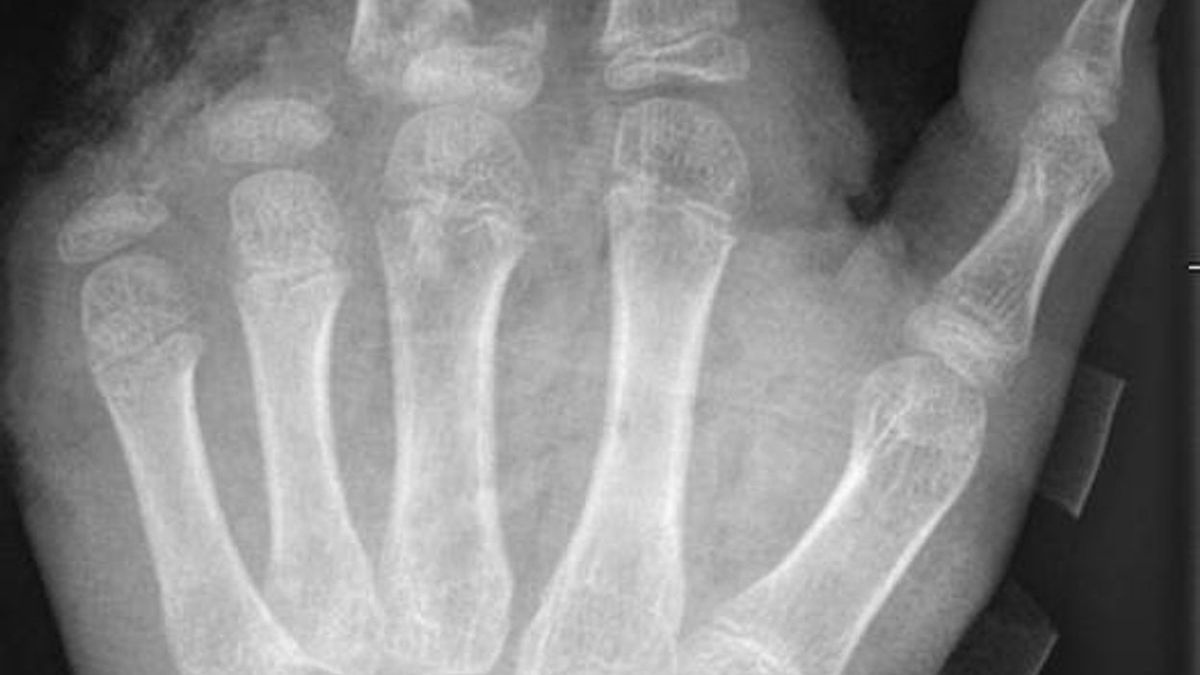

In der Handchirurgie müssten an Silvester im Unfallkrankenhaus rund 20 bis 40 Menschen mit Böllerverletzungen operiert werden, sagt die Ärztin. Dieses Jahr werde sie mir vier weiteren Handchirurgen im Einsatz sein. Die häufigsten Verletzungen entstünden durch explodierende Böller in der Hand.

«Der überwiegende Teil der Verletzungen trägt tatsächlich lebenslange Folgen mit sich, weil die Sprengkraft dazu führt, dass eben nicht nur einzelne Strukturen verletzt sind, sondern immer mehrere. Und das heilt praktisch nie ganz folgenlos ab.» Zum Teil könnten Hände nicht mehr gerettet und müssten amputiert werden.

Für eine neue Dimension habe im vergangenen Jahr das illegale Abbrennen von Kugelbomben gesorgt. «Die Patienten mit Verletzungen durch Kugelbomben weisen sehr viel stärkere Verletzungsmuster auf, die auch den ganzen Körper betreffen, weil diese Explosion ungerichtet stattfindet. Und das sind nicht nur Hände und Gesichter, sondern auch Bauch, Beine.» Alle Körperareale seien gleichermaßen gefährdet.